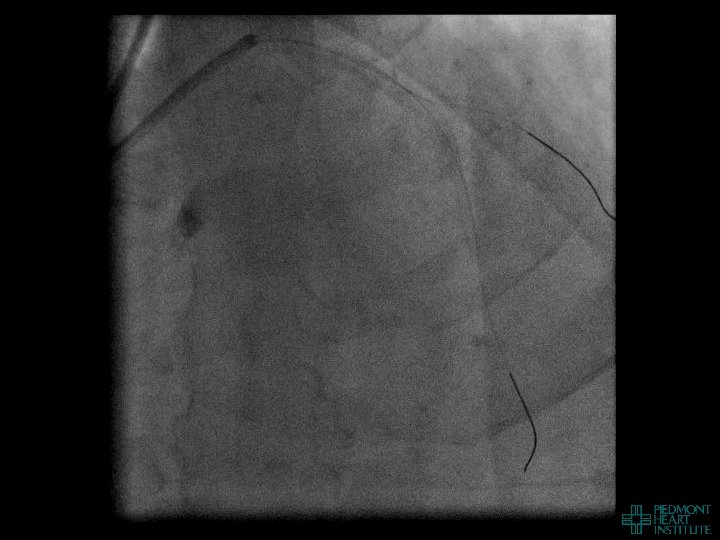

Coronary Perforation in CTO Revascularization Management Issues David E. Kandzari, MD, FACC, FSCAI david. kandzari@piedmont. org Director, Interventional Cardiology, Piedmont Heart Institute Chief Scientific Officer, Piedmont Heart Institute Atlanta, Georgia

Coronary Perforation In CTO Revascularization Often does not occur at the occluded segment nor

Coronary Perforation In CTO Revascularization Often does not occur at the occluded segment nor is related to the guidewire… 12% CTO-related perforations due to balloon inflation, stent implantation, or atherectomy 1 Is not always manifest during the procedure… 45% events diagnosed after leaving the catheterization laboratory (mean time from PCI 4. 4 hrs)2 Is associated with substantial morbidity and mortality… Death (42%), emergency surgery (39%), MI (29%), transfusion (65%)2 1 Nakamura et al. AHA 2002, 2 Fejka, O’Neill et al. AJC 2002

Coronary Perforation Methods of Patient Management • Dual Catheter (‘Ping Pong’) Technique • Prolonged

Coronary Perforation Methods of Patient Management • Dual Catheter (‘Ping Pong’) Technique • Prolonged balloon inflation and covered stents • Reversal of anticoagulation — Know contradictions to protamine sulfate for UFH; Avoid bivalirudin, LMWH — Reserve GP 2 b 3 a inhibition until successful crossing and wire change-out Embolization • — Coil, gelfoam, methacrylate, autologous blood/fat • Microcatheter Occlusion • Confirmation of successful management — Contralateral injection — Right heart catheterization — Echocardiogram — Contrast echocardiography